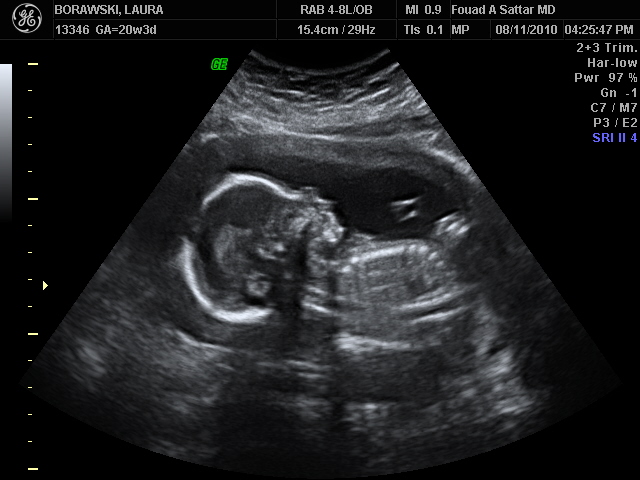

On the 9th, we went back for a repeat ultrasound to see the baby. This time, the baby opened up and showed the world to all. And, for once, a baby decided to show the goods for us to see. Well, Gwenna is now going to have another girl to compete with around the house :-) Although, I've realized recently, that it's probably a good thing that Gwenna has a side-kick. As I mentioned above, Miles is quickly outgrowing Gwen, so maybe there's safety in numbers! Everything else about the appointment was good. Her heartbeat was 156bpm and my blood pressure was 116/70. They did mention, based on my ultrasound, that the placenta is low. Which, right now, is no risk to either the baby or me, but if it happens to migrate lower, there is a potential for a c-section and bedrest closer to the end. The chances of it migrating lower are slim, as it tends to migrate up to a better blood supply. I'll be going back for a follow-up ultrasound when I'm 32 weeks so see which way it has migrated. So, I'll be back in a few weeks with my next update. I'll be back later with pictures :-)

Laura update: I guess we can say a new year another pregnancy! That's right, we're working on cooking #3, and almost half way done too :-P Yesterday, we went to have the anatomy ultrasound to make sure that everything was happy and healthy with the baby. While everything looked great from what they could see, the baby stayed curled up in a little ball and refused to cooperate. So, I get to have another ultrasound in 4 weeks to see if the baby will cooperate that time. Gwenna, when we tried to explain that Mommy was pregnant again, called the baby "Happy", so that's what we have taken to calling the baby until we know otherwise. I'm sure I've this mentioned before, but Brian and I have decided from here on out to let the baby decide if they wanted us to know their gender before their birthday. Well, the baby decided not to show us at yesterday's ultrasound, but I think we'll try to take a look at the next appointment just because we get a second chance. Everything else from the appointment looked great.